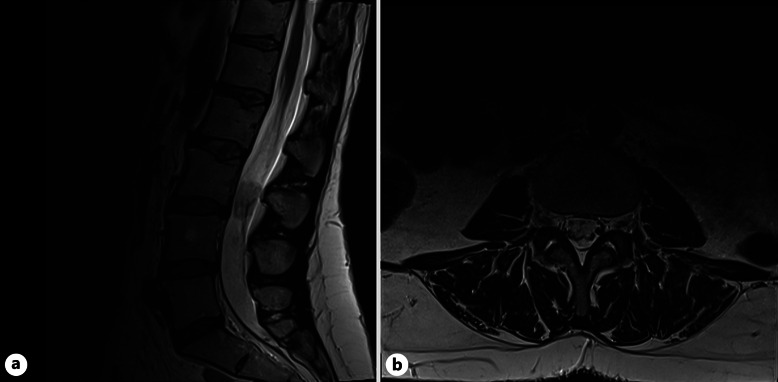

Case summary: A 46-year-old female presented with a 3-month history of worsening back pain. Reduced sensation on the right side in L1, L2, and per rectum was found on examination. MRI displayed a L3 IDEM mass. Background was significant for childhood PA, debulked at age 8 and 13. Right L3 hemilaminectomy and subtotal resection was performed. The mass was found to be composed of pleomorphic astroglial cells and was glial fibrillary acidic protein-positive with a fusion between exon 16 of KIAA1549 and exon 9 of BRAF. A recurrence of pilocytic astrocytoma in the lumbar spine was diagnosed, over 38 years after previous treatment.

Abstract Image